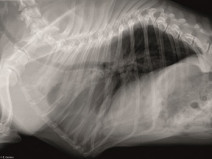

• Bases de l’échographie abdominale (module central - niveau de base) : Nantes

Public visé : La formation est ouverte aux docteurs vétérinaires qui souhaitent offrir au sein des établissements de soin vétérinaire des prestations de qualité accrue en échographie des animaux de compagnie

Prérequis : Être docteur vétérinaire. évoluer dans une structure de soins vétérinaires disposant d’un échographe ou vouée à en disposer dans un...

Du 14 au 15 octobre 2017

La-Chapelle-sur-Erdre (44242)

Imagerie Médicale

G.E.I.M.

234